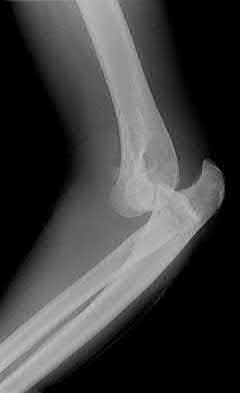

1020) Figures 108a through 108c are the radiographs of a 38-year-old man who fell on an outstretched hand 1 week ago and now reports severe left elbow pain. Examination of the wrist reveals normal range of motion with no tenderness or swelling. Pain limits examination of his elbow. What is the most appropriate management to determine if surgery is indicated?

1. CT of the elbow

2. MRI of the elbow

3. Apply a long-arm splint and schedule a follow-up examination in 2 to 3 weeks when less painful

4. Examination under general anesthesia

5. Intra-articular lidocaine injection followed by repeat examination Corrent answer: 5

Whereas there is controversy regarding the best treatment for comminuted radial head fractures, nondisplaced and minimally displaced fractures in which there is no block to motion can be treated nonsurgically. At the time of initial examination, it is important to determine that there is no block to range of motion. If pain limits the ability to examine the patient's range of motion, local analgesia with intra-articular lidocaine is most appropriate. Whereas general anesthesia would be useful for open reduction and internal fixation, the necessity for open reduction and internal fixation is best determined first before scheduling surgery. Neither a CT or MRI scan is necessary if the patient has no block to range of motion. Early range of motion is the best treatment for radial head fractures treated nonsurgically. After immobilization for 2 weeks, it may be difficult to determine whether there is a block to motion because the patient will likely have decreased elbow pronation and supination.